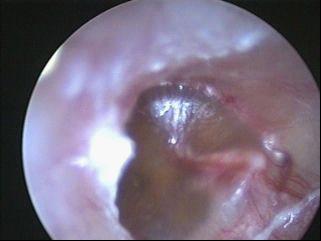

忽视“耳底子”终致胆脂瘤型中耳炎!

28岁的樊先生患胆脂瘤型中耳炎,一年前耳朵只是隐隐作痛伴有间断流脓,期间也是有过保守对症治疗,但一年下来症状并不见治疗。今年六月初,樊先生听力明显下降,耳朵痛得晚上几乎无法入眠。科...[详细]